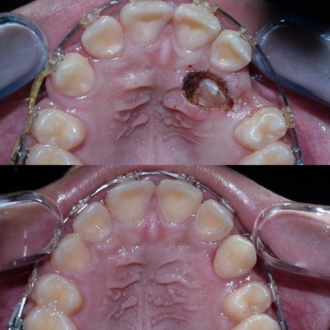

Перелечивание корневых каналов. Пациент обратился с признаками воспалительного процесса в верхнем зубе. Выявлены незапломбированные корневые каналы. Выполнен тщательное перелечивание с последующим герметическим пломбированием.

Пациент нуждался в повторном лечении корневых каналов из-за осложнений предварительного лечения. Выполнено извлечение анкерного штифта, перелечивание корневых каналов, очищение и пломбирование с учетом анатомических особенностей зуба.

Во время диагностики обнаружен отлом фрагмента инструмента в корневом канале. Выполнено его безопасное извлечение, повторное перелечивание каналов, очистку и герметичное пломбирование.

Перелечивание с удалением двух переломанных инструментов. Пациент обратился с осложнением предварительного эндодонтического лечения. В каналах были обнаружены два переломанных инструмента. Выполнены их удаление и пломбирование каналов с соблюдением современных эндодонтических протоколов.

Перелечивание корневых каналов. Пациент обратился с симптомами, свидетельствующими о недостаточном предварительном лечении. Выполнены перечисления корневых каналов, тщательная очистка и повторная пломбировка для достижения полной герметичности и предотвращения рецидива воспаления.

Первичное лечение корневых каналов. Лечение пульпита, возникшего вследствие глубокого кариеса.